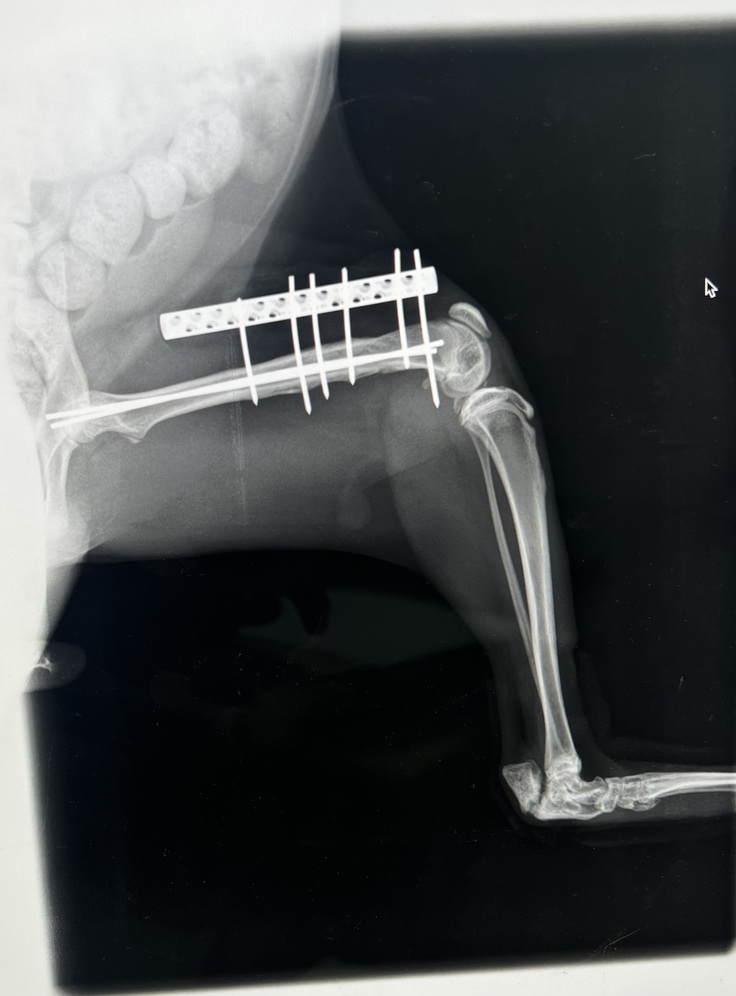

▲左脚のレントゲン画像

順調すぎるほど順調に骨折は回復してきています❤️🩹

綺麗に折れた骨はくっついてました🦴!!

アンジュちゃんは若いこともあり思ったよりも治りが早いみたいです✳︎